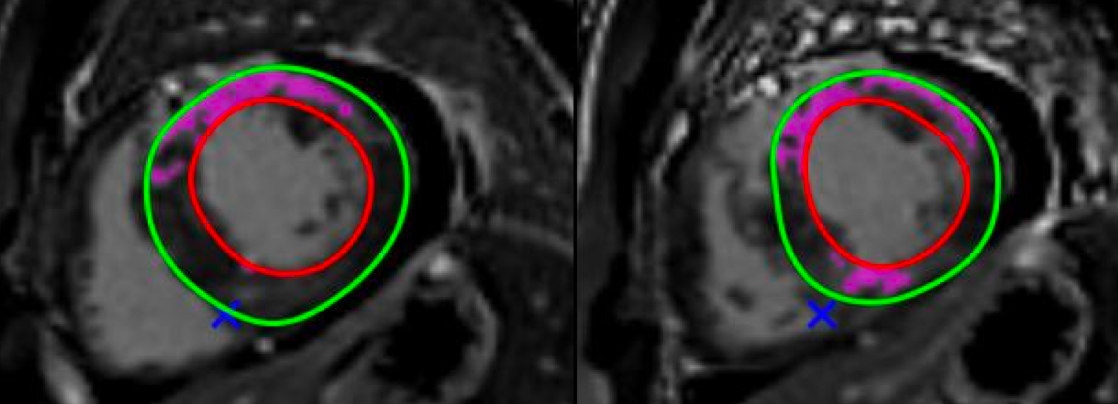

Risk stratification in HCM